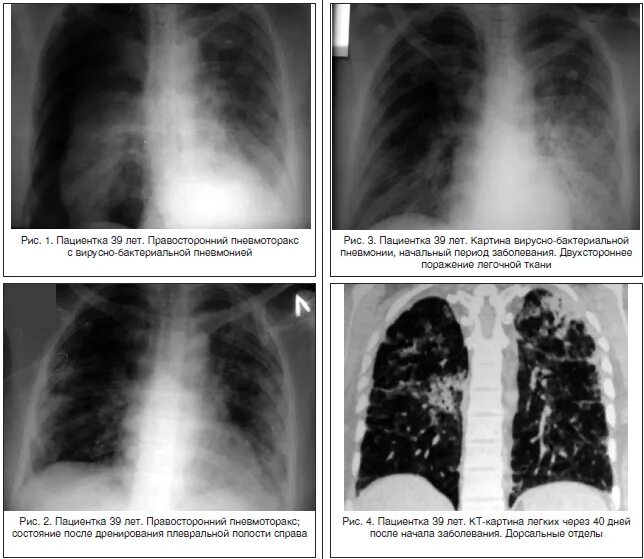

Пневмония сколько поражение легких